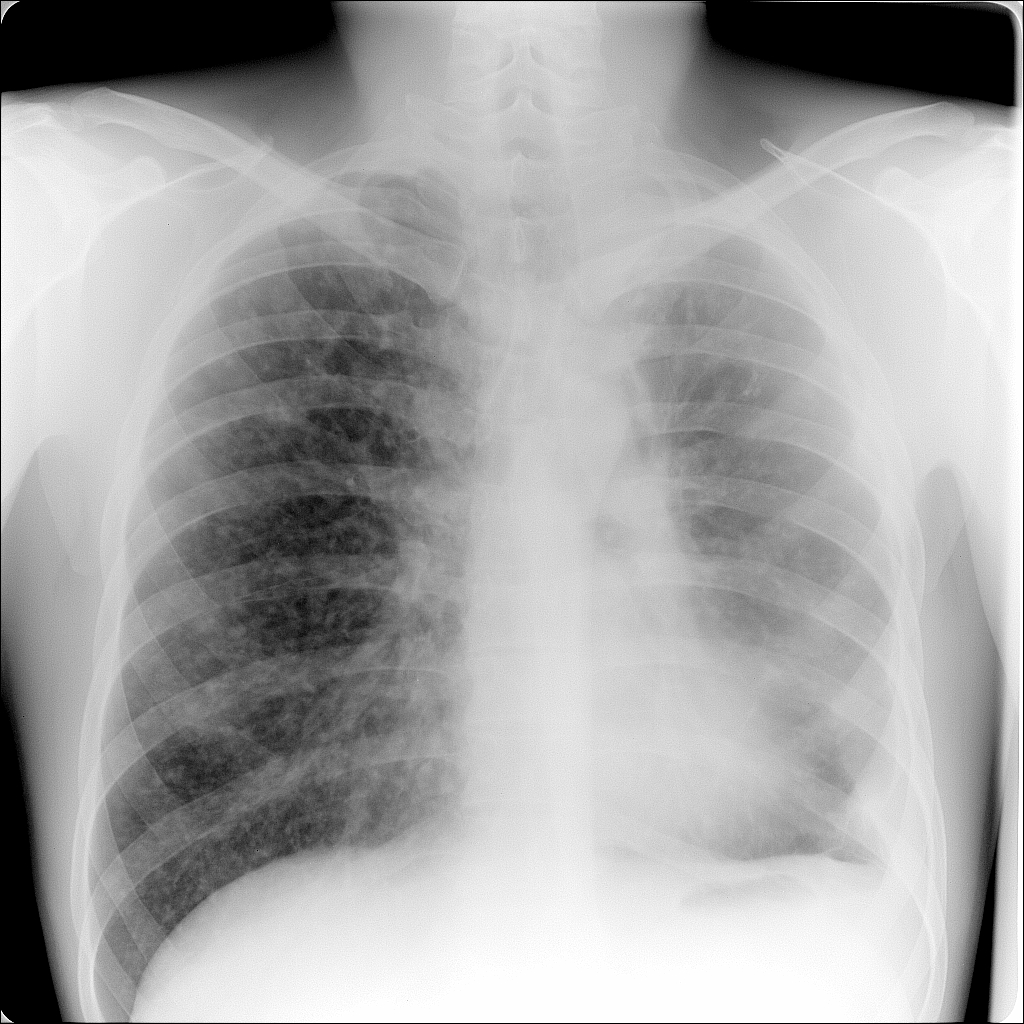

Снимок легких при туберкулезе является важным методом диагностики этого заболевания. На рентгеновских снимках можно увидеть изменения в легких, которые свойственны туберкулезу.

Диссеминированный туберкулез на рентгенограмме

Диссеминированный туберкулез рентген

Диссеминированный туберкулёз лёгких рентген

Фотографии снимков легких при туберкулезе

В данной статье представлены многочисленные фотографии снимков легких при туберкулезе, чтобы помочь вам понять, как выглядят изменения легких на рентгеновских снимках при этом заболевании.